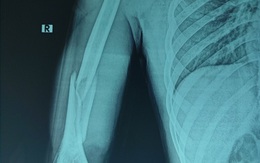

Nam thanh niên 18 tuổi gãy xương khi chơi vật tay với bạn

Trong lúc vui đùa, nam thanh niên 18 tuổi cùng bạn thi vật tay. Sau đó một tiếng rắc vang lên, kèm theo cảm giác đau dữ dội ở cánh tay phải.

Nam thanh niên tập gym bị gãy xương khi chơi vật tay

Sau khi chơi vật tay cùng bạn, nam thanh niên 21 tuổi nhập viện trong tình trạng cánh tay sưng đau, biến dạng, hạn chế vận động.